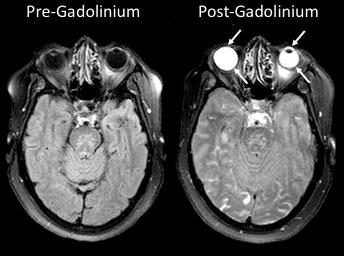

Research into curious bright spots in the eyes on stroke patients' brain images could one day alter the way these individuals are assessed and treated. A team of scientists at the National Institutes of Health found that a chemical routinely given to stroke patients undergoing brain scans can leak into their eyes, highlighting those areas and potentially providing insight into their strokes. The study was published in Neurology .

The eyes glowed so brightly on those images due to gadolinium, a harmless, transparent chemical often given to patients during magnetic resonance imaging (MRI) scans to highlight abnormalities in the brain. In healthy individuals, gadolinium remains in the blood stream and is filtered out by the kidneys. However, when someone has experienced damage to the blood-brain barrier, which controls whether substances in the blood can enter the brain, gadolinium leaks into the brain, creating bright spots that mark the location of brain damage.

The researchers performed MRI scans on 167 stroke patients upon admission to the hospital without administering gadolinium and compared them to scans taken using gadolinium two hours and 24 hours later. Because gadolinium is transparent, it did not affect patients' vision and could only be detected with MRI scans. Roughly three-quarters of the patients experienced gadolinium leakage into their eyes on one of the scans, with 66 percent showing it on the two-hour scan and 75 percent on the 24-hour scan. The phenomenon was present in both untreated patients and patients who received a treatment, called tPA, to dissolve the blood clot responsible for their strokes.